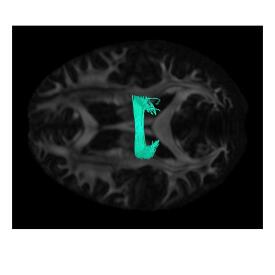

We performed k-means clustering and manually selected pairs of fibers from clusters most similar to major bundles. We then modeled these fibers using different computational models, and analyzed the impact of varying the kernel bandwidth parameters. The range of these parameters were estimated by observing the values of distance between centers of fiber segments and difference between along tract GFA values for selected multiple pairs of fibers. Figure 1 (top left) shows GFA color-coded fibers for pairs corresponding to a) right Corticospinal tract – CST (R), b) Corpus Callosum – CC, and c) right Inferior Fronto-Occipital Fasciculus – IFOF (R). Cosine similarity (in degrees) is reported for the fiber pairs modeled using varifolds (Var) and functional varifolds (fVar), for = 7 mm and = 0.01.

Figure 1 (top left) shows GFA color-coded fiber pairs. The color-coded visualization reflect the variation of fiber geometry, microstructure measure (i.e. GFA) along fiber, and difference in GFA along fiber for the select fiber pairs. This visualization of variation and difference in GFA values along fibers support our hypothesis that modeling along tract signal along with geometry provides additional information. The change in cosine similarity for CC from degrees (using varifolds) to degrees (using functional varifolds) while for CST (R) from degrees to degrees, reflect more drop in cosine similarity if along tract signal profiles are not similar. This shows that functional varifolds imposes penalty for different along fiber signal profiles.